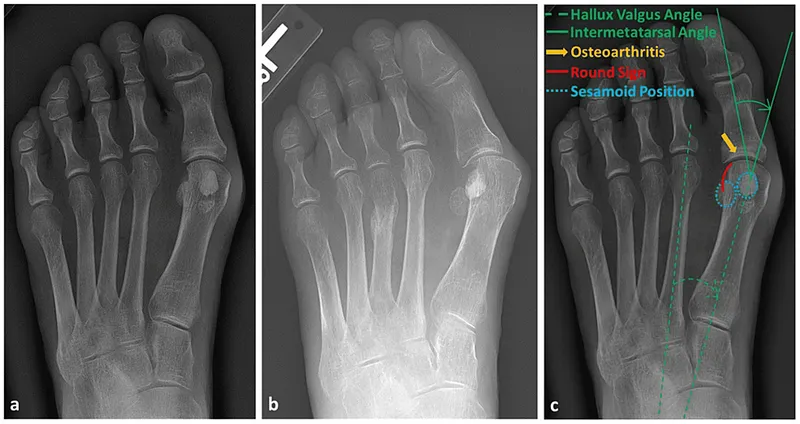

Radiographic Evaluation (Weight-bearing AP & Lateral views):

- Key angles for severity & surgical planning:

| Angle | Normal | Mild | Moderate | Severe |

|---|---|---|---|---|

| Hallux Valgus Angle (HVA) | < 15° | 15-20° | 21-39° | ≥ 40° |

| Intermetatarsal Angle (IMA) | < 9° | 9-11° | 12-15° | ≥ 16° |

| Distal Metatarsal Articular Angle (DMAA) | < 10° |

- Assess joint congruity, arthritis, sesamoid position (📌 AP view).